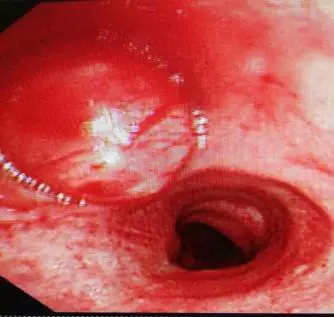

入院后普通气管镜检查如图:

肿瘤完全阻塞左主支气管,肿瘤新生物血管丰富。考虑到内镜介入治疗出血和窒息风险很高,科室讨论后决定行硬质气管镜下肿瘤切除术。